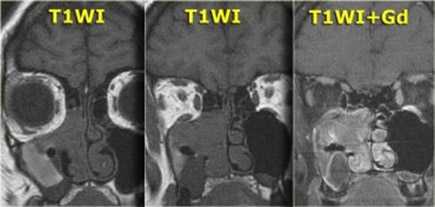

Один пациент, по данным КТ височных костей, имел двустороннюю облитерацию лабиринта, включая улитки с двух сторон, с большей выраженностью патологических изменений справа. На МРТ было выявлено уменьшение количества жидкости в улитке справа, слева количество жидкости в улитке соответствовало норме (рис. 1, 2).

Рис. 1. КТ, аксиальная проекция. Облитерация улитки (стрелка).

Рис. 2. МРТ, аксиальная проекция. Справа — полное отсутствие жидкости в улитке (короткая стрелка), слева — частичное (длинная стрелка).